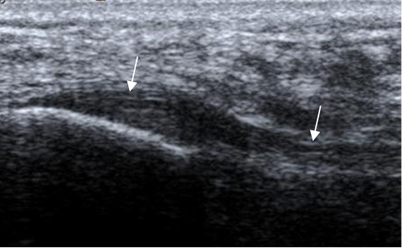

Fig 21. Fascia plantar normal en ecografía, corte sagital.

La parte anterior del tendón es plana o levemente cóncava, en los cortes axiales (2) y es mejor estudiado en las secuencias sagitales. (1). Presenta con algunas áreas con SI intermedia en T1 y DP, que corresponden a vasos o septos (2) y en ocasiones mínima cantidad de líquido se encuentra en la vaina del tendón, que no es clínicamente significativa. (1). (Fig 22, 23 y 24).

Fig 22. Tendón de aquiles normal en ecografía, corte sagital.

A: Tercio medio y B: En su inserción.